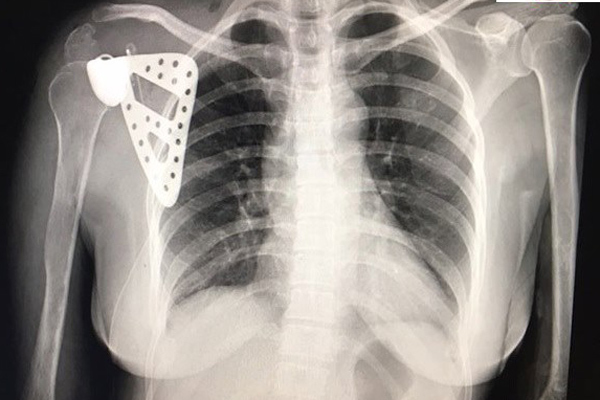

Chủ quan với cơn đau bả vai, cô giáo Hà Nội bị ung thư xương mà không biết

- Chị Thúy chịu đựng cơn đau âm ỉ như kiến cắn ở bả vai suốt 5 năm. Chỉ đến khi không nâng tay được mới đi khám, bác sĩ kết luận đã bị ung thư.